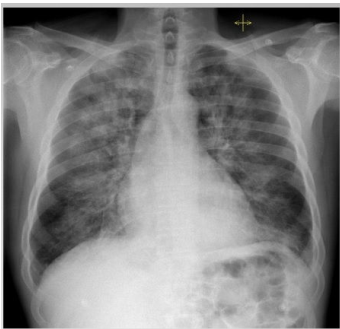

Analise a seguinte imagem.

Considerando a radiografia de tórax anterior, é correto afirmar que

Analise a seguinte imagem.

Considerando a radiografia de tórax anterior, é correto afirmar que